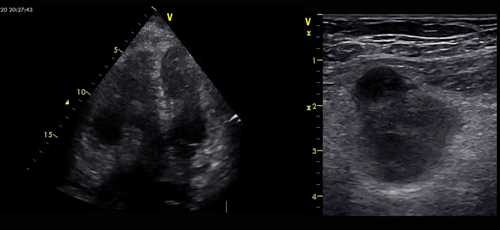

Echo cardio + Echo 4 points :

Fonction VG conservée

Dilatation des cavités droites

Thrombus mobile de l’OD et VD de 5 cms